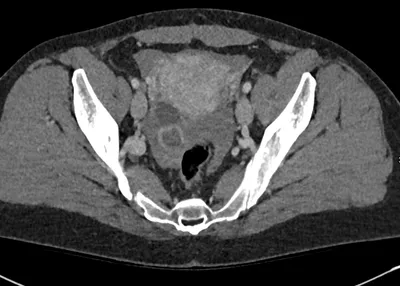

Ischiofemoral space injection for ischiofemoral impingement

CTPelvisAxial+2